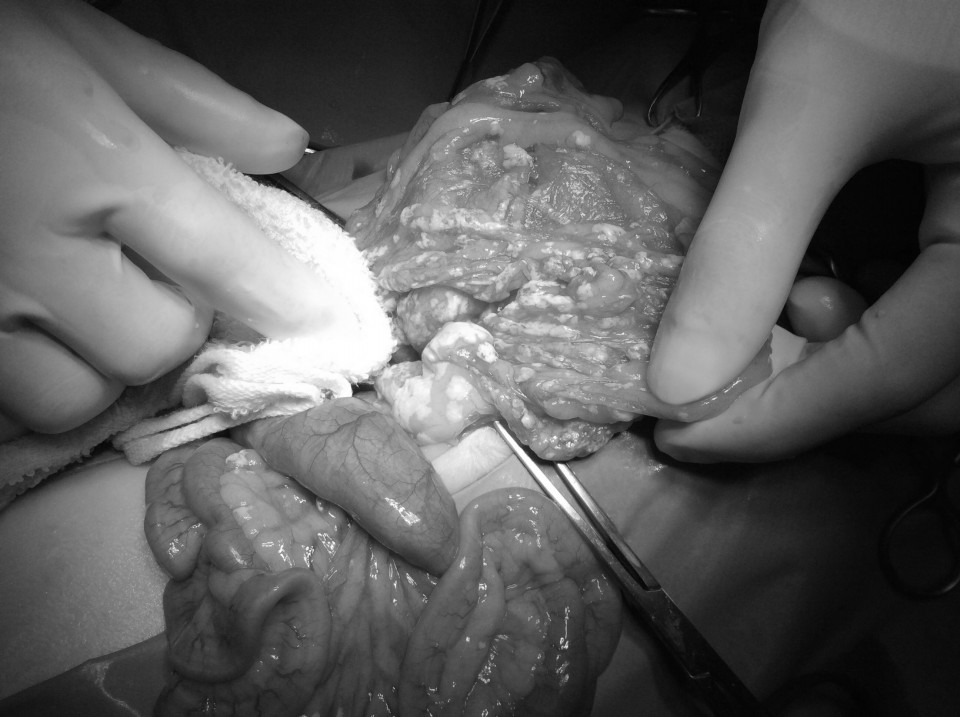

case.1

結腸から直腸に発生した未分化型リンパ腫。

ミニチュアダックスフント、8歳齢、避妊雌。

肛門からの脱腸を繰り返し、結腸粘膜の組織生検で未分化型リンパ腫と診断。

L-CHOP療法を中心とした多剤併用化学療法を実施。寛解するも早期再燃し、ACNU、CCNU、DTICでサルベージ療法を実施。